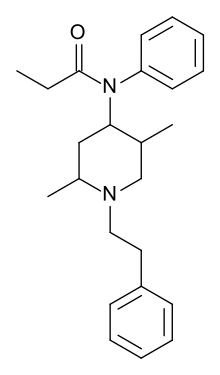

Anilidopiperidines

- 3-Allylfentanyl

- 3-Methylfentanyl

- 3-Methylthiofentanyl

- 4-Phenylfentanyl

- Alfentanil

- α-Methylacetylfentanyl

- α-Methylfentanyl

- α-Methylthiofentanyl

- Benzylfentanyl

- β-hydroxyfentanyl

- β-hydroxythiofentanyl

- β-Methylfentanyl

- Brifentanil

- Butyrfentanyl

- Carfentanil

- Fentanyl

- Lofentanil

- N-Methylcarfentanil

- Mirfentanil

- Ocfentanil

- Ohmefentanyl

- Parafluorofentanyl

- Phenaridine

- R-30490

- Remifentanil

- Sufentanil

- Thenylfentanyl

- Thiofentanyl

- Trefentanil

Structures